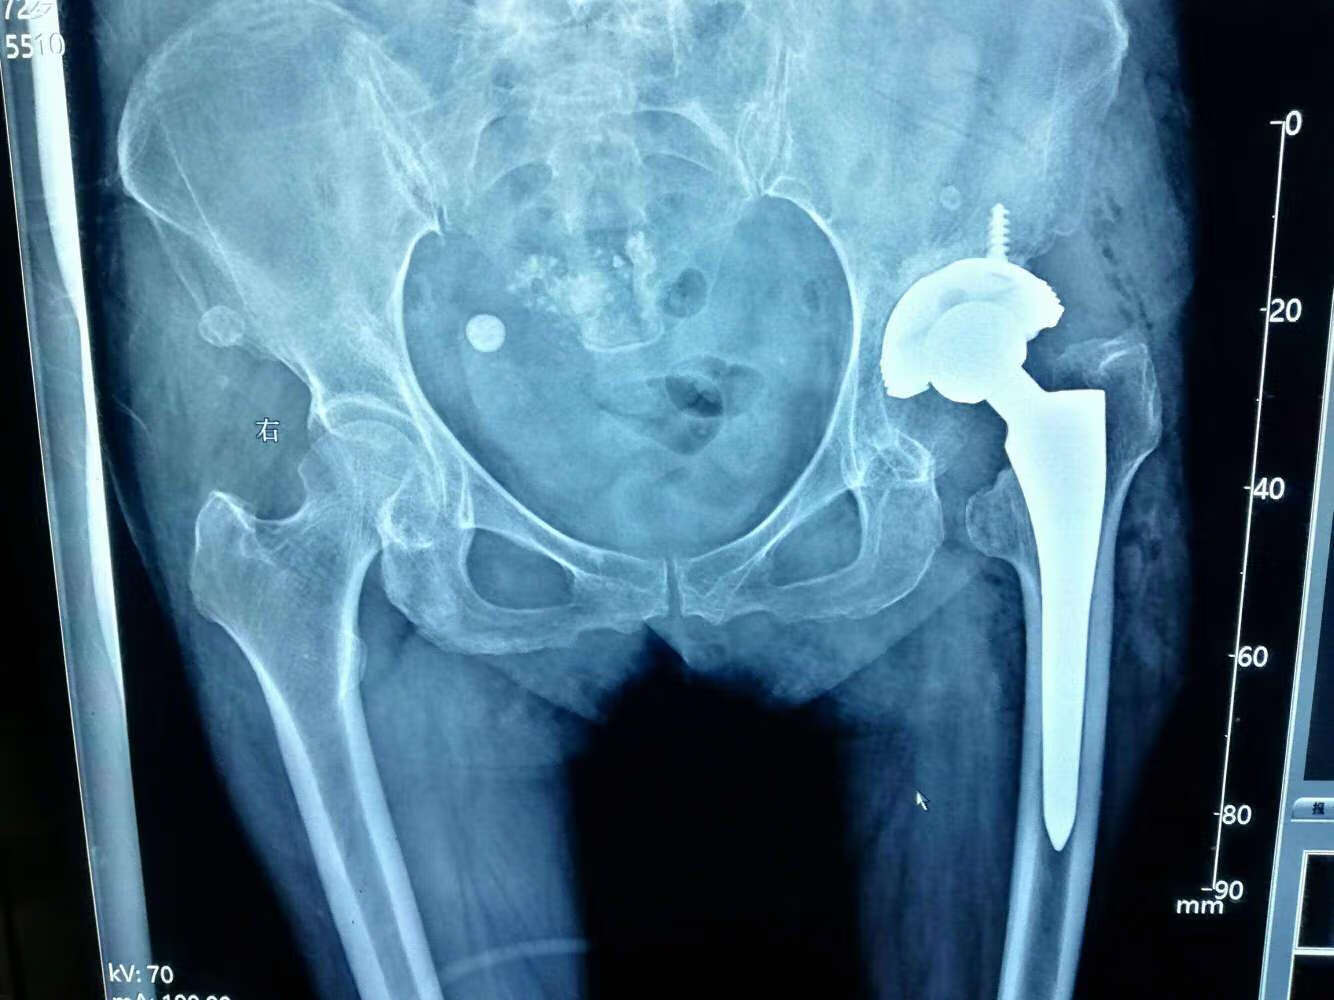

在手术方面,常见的方法有关节置换手术、内固定术等。这类手术通常适用于病情较重的患者。关节置换手术可以有效地消除疼痛,并改善生活质量;而内固定术则意在恢复股骨头的血供,以促进自愈。根据病例统计,这两种手术方式在效果上各有优缺点,患者可根据自身情况与医生讨论选择合适方案。